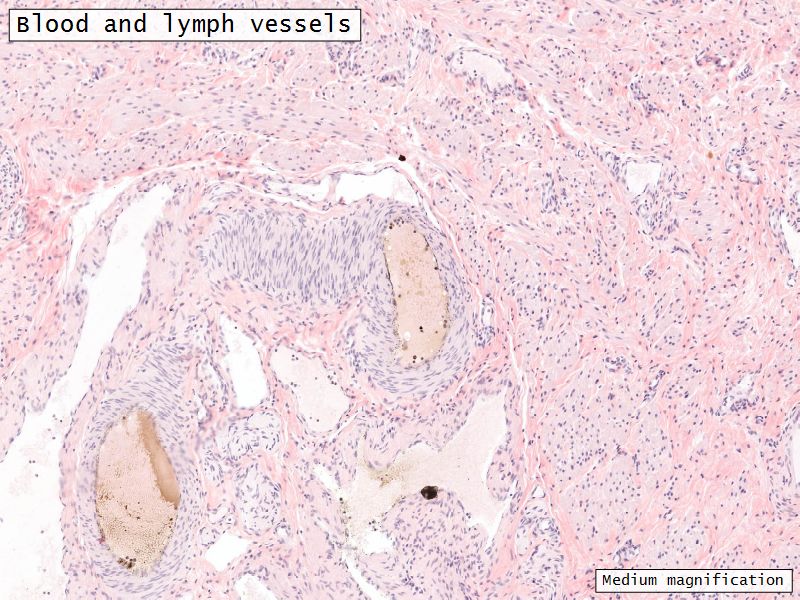

Blood vessels

- Enter medulla at hilus

- Supply the cortex

- Epithelioid cells clump around blood vessels